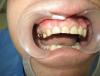

iБолит Опубликовано 21 января, 2013 Поделиться Опубликовано 21 января, 2013 Первый вопрос диастемой - почему ее решили закрыть? Ортодонтия или будушая работа с клыком погла ее решитьВторое -поднять прикус и делать весь верх, это помогло бы добиться лучших результатовТретье - если делали инд абатмент почему он не индивидуален? Понимаете почему светится у шейки? то место которое образовалось оно чем закрылось? десну не дотяните и будет полость, даже если цементом залили ничего хорошего. Как спасение может быть композитом попробовать ( чисто догадка) Серьезно смотрится не очень удачно когда ширина больше 11 зубаИ еще одно. проблема с цветом как никак.Из луших пожеланий говорю, а не так чтобы подстегнуть, просто очень много ошибокНо однозначно переделывать Ссылка на комментарий

anvladd Опубликовано 21 января, 2013 Автор Поделиться Опубликовано 21 января, 2013 Переделывать не буду, пац доволен(пришел только с этим зубом).Про диастему честно и не думал.Весь верх делать предлагал, отказался!На счет абатмента тоже расстроился когда работа пришла, но выбора не было, пришлось ставить его. Пустота ничем не закрылась,получился нависающий край коронки.Это моя первая работа на инд абатменте и цирконе. Цель была поставить зуб и не заморачиваться на эстетике. Ссылка на комментарий

iБолит Опубликовано 21 января, 2013 Поделиться Опубликовано 21 января, 2013 Осторожнее с этим. Это не нависающий край а полость целая. Учитывайте на будущее. Ссылка на комментарий